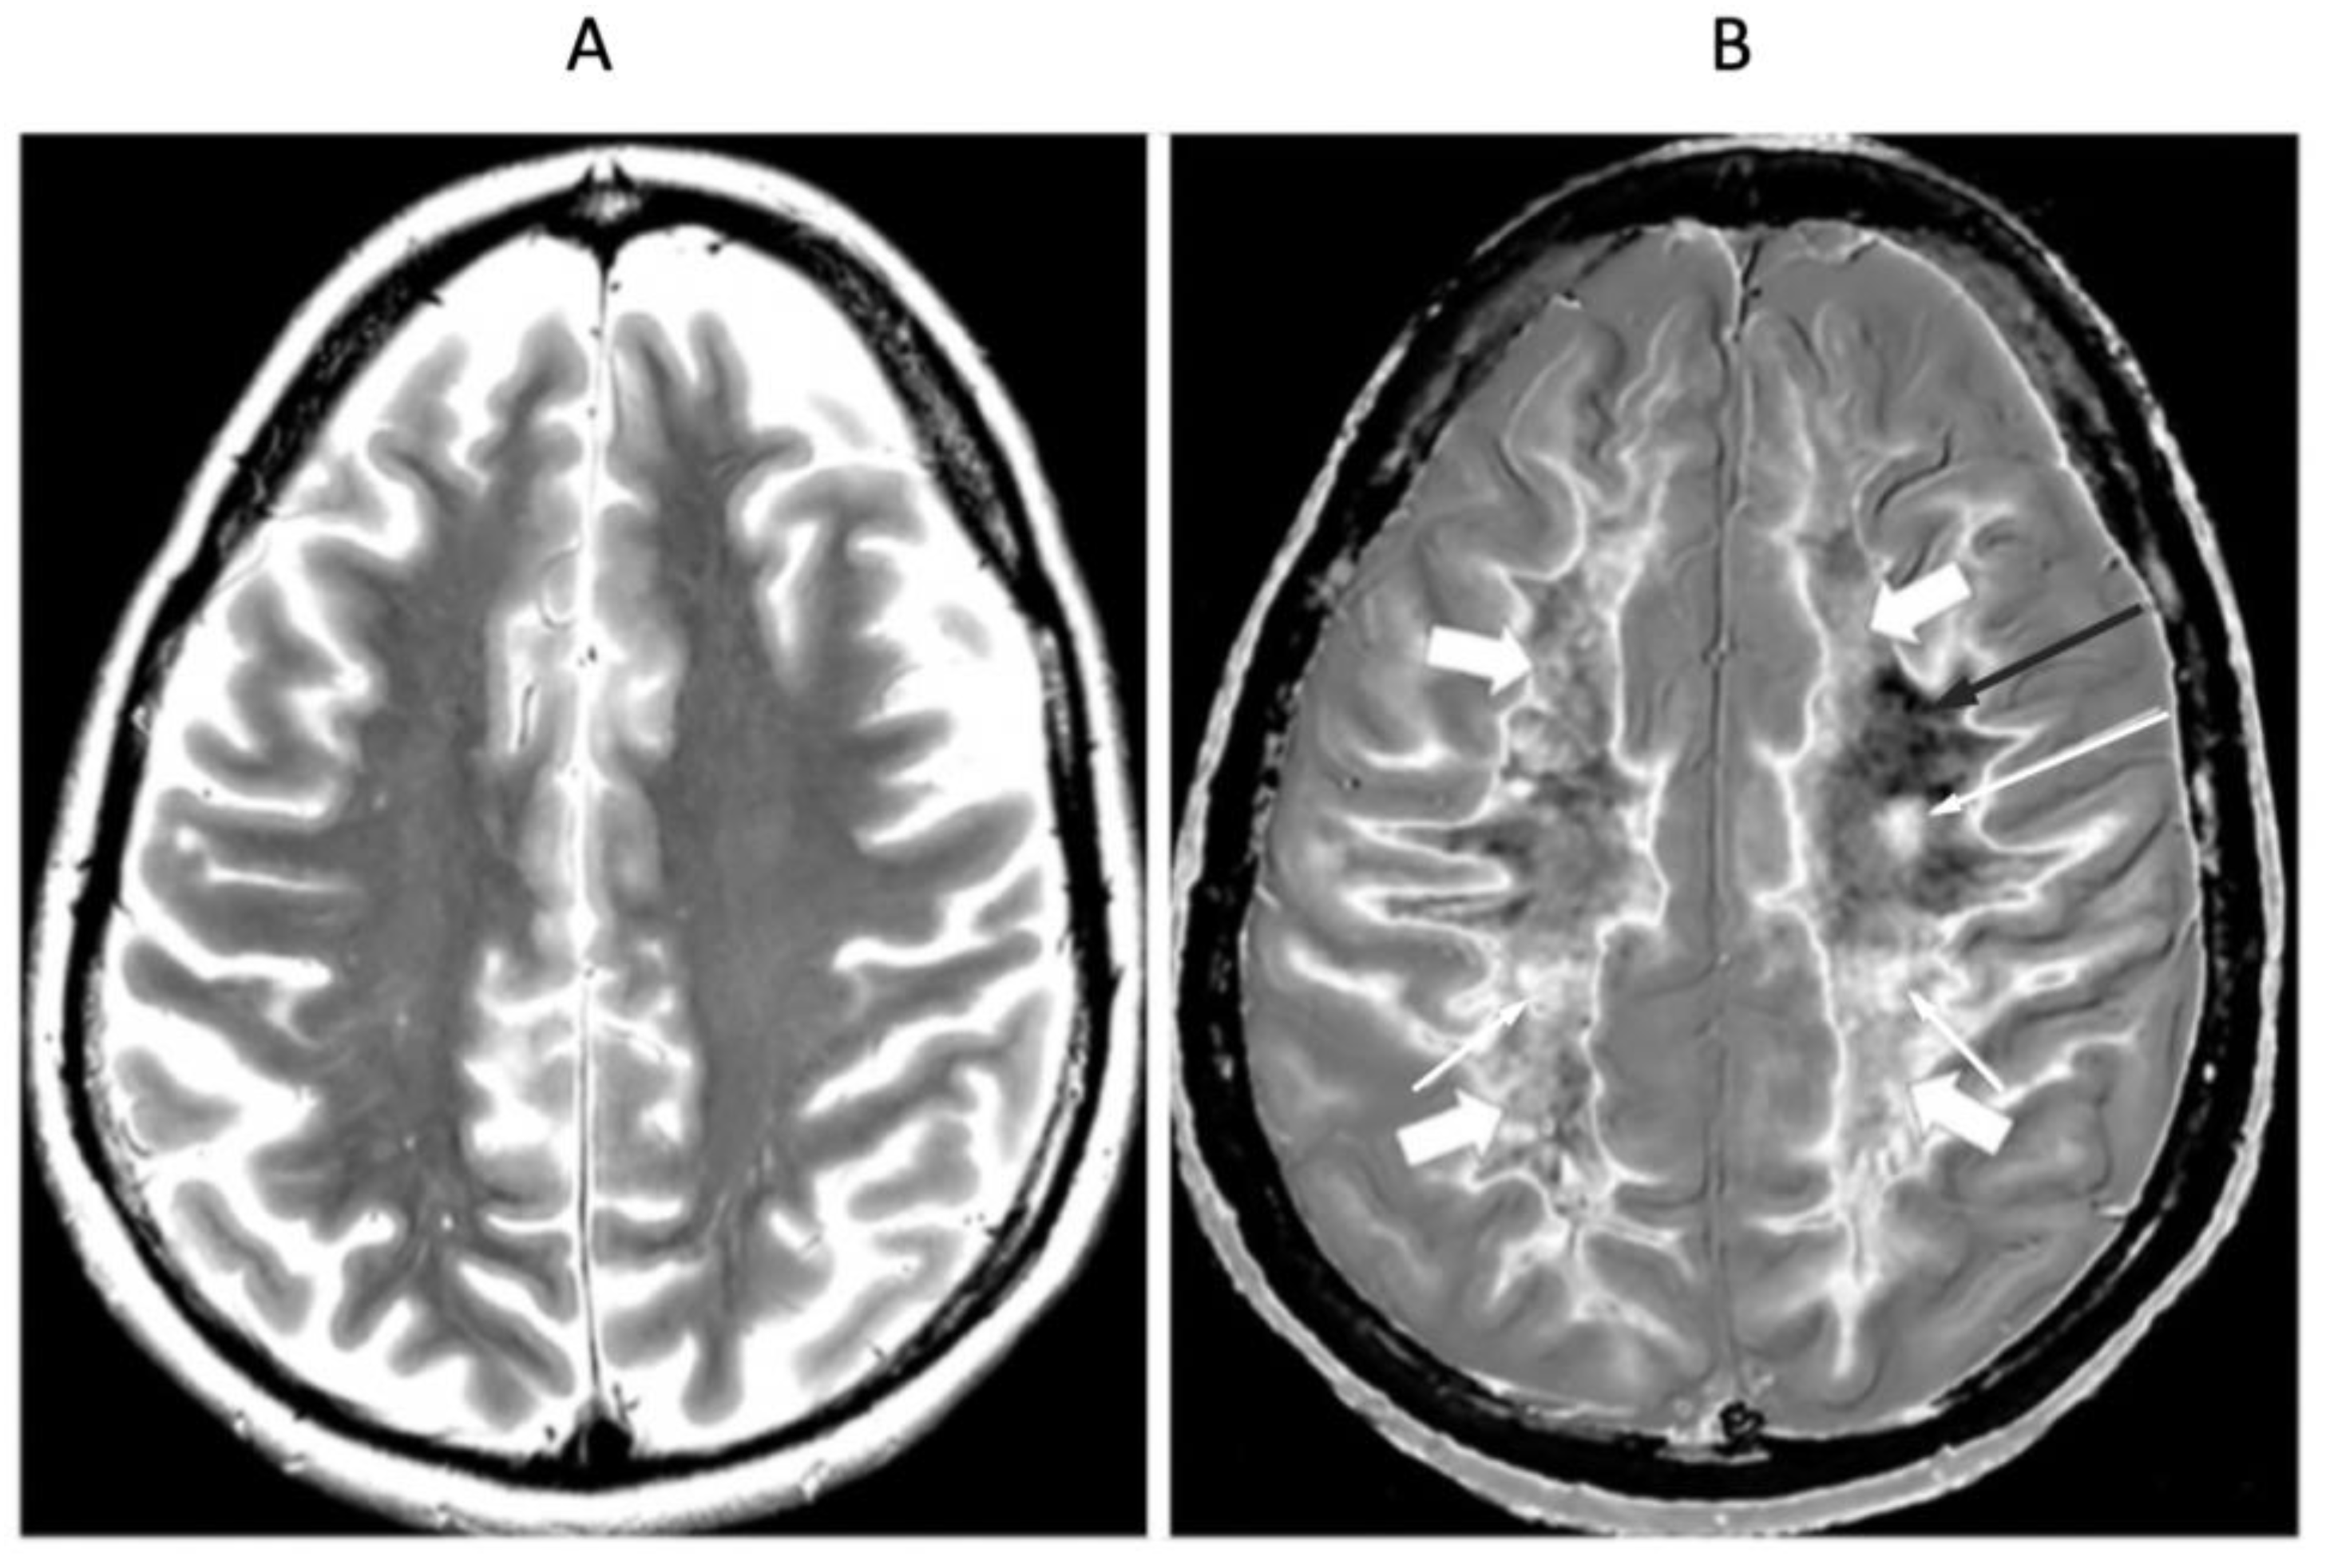

Figure 8 shows positionally matched supraventricular T2-FLAIR (Figure 8A) and narrow mD dSIR (Figure 8B) images in a patient with MS during a relapse. A single lesion is seen on the T2-FLAIR image, and this is also seen on the dSIR image (long white arrows). An additional six lesions are only seen on the dSIR image (short white arrows). Many of the lesions on the dSIR image have high signal boundaries (rims). In addition, there are bilateral symmetrical widespread relatively uniform increases in signal in white matter, with some sparing of more peripheral white matter. These are features of a high grade (4–5) (maximum grade 5) whiteout sign [6]. This differs from the normal dark appearance of white matter seen on the narrow mD dSIR image in Figure 6B. No evidence of a whiteout sign is seen on the T2-FLAIR image.

Figure 8.

Thirty-two-year-old female patient with MS undergoing a relapse. T2-FLAIR (A) and synthetic narrow mD dSIR (B) images. On the T2-FLAIR image, one lesion is seen (long arrow). The surrounding white matter appears normal. On the dSIR image (B), the lesion shown on the T2-FLAIR image is seen (long arrow) as well as six other lesions (short arrows). Most of the white matter in (B) is high signal corresponding to a high grade 5 (out of 5) whiteout sign [7]. This is in contradistinction to the appearance of the peripheral white matter in the patient with MS in remission shown in Figure 6B. where the peripheral white matter is low signal.

Figure 9 and Figure 10 show a 38-year-old patient with MS in remission (Figure 9A and Figure 10A, left columns) and during a relapse two years and five months later (Figure 9B and Figure 10B, right columns) imaged with the same narrow mD dSIR sequence. Figure 9 shows three positionally matched lower levels in the brain and Figure 10 shows two positionally matched higher levels in the brain. White matter shows a generally low signal during remission (whiteout sign grade 1–2) (Figure 9A and Figure 10A), and a high signal (whiteout sign grade 4–5) during the relapse (Figure 9B and Figure 10B). The multiple levels within the brain show the wide distribution of the high grade whiteout sign in the cerebellar and cerebral hemispheres, as well as in the brainstem. No evidence of a whiteout sign was seen on the corresponding T2-FLAIR images.

Figure 9.

Thirty-eight-year-old female patient with MS in remission (A, left column) and during a relapse (B, right column) two years and five months later. Matching narrow mD dSIR images at three lower levels in the brain. In remission (left column), there are bilateral symmetrical areas of low signal in the white matter of the cerebellar and cerebral hemispheres. The corresponding areas show increased signal during the relapse (right column) consistent with a grade 4–5 (out of 5) whiteout sign. No evidence of a whiteout sign was seen on the T2-FLAIR images.